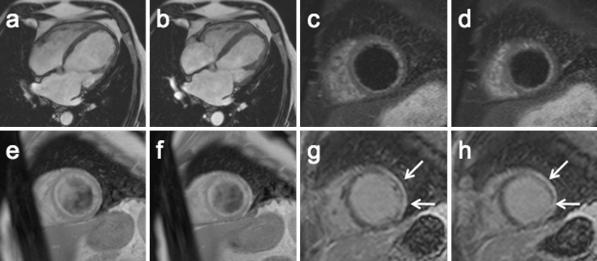

Our objective was to evaluate the ability of CMR to visualize myocardial injuries over the course of myocarditis. We studied 42 patients (39 males, 3 females; age 37 ± 14 years) with myocarditis during the acute phase and after 12 ± 9 months. CMR included function analyses, T2-weighted imaging (T2 ratio), T1-weighted imaging before and after i.v. gadolinium injection (global relative enhancement; gRE), and late gadolinium enhancement (LGE). In the acute phase, the T2 ratio was elevated in 57%, gRE in 31%, and LGE was present in 64% of the patients. In 32 patients (76%) were any two (or more) out of three sequences abnormal. At follow-up, there was an increase in ejection fraction (57.4 ± 11.9% vs. 61.4 ± 7.6; P < 0.05) while both T2 ratio (2.04 ± 0.32 vs. 1.70 ± 0.28; P < 0.001) and gRE (4.07 ± 1.63 vs. 3.11 ± 1.22; P < 0.05) significantly decreased. The LGE persisted in 10 patients. Dilated cardiomyopathy was present in 3 patients and 4 patients received a defibrillator or a pacemaker. A comprehensive CMR approach is a useful tool to visualize myocardial tissue injuries over the course of myocarditis. CMR may help to differentiate acute from healed myocarditis, and add information for the differential diagnoses.

我们的目的是评估心脏磁共振(CMR)在心肌炎病程中观察心肌损伤的能力。我们研究了 42 例急性心肌炎患者(男 39 例,女 3 例;年龄 37 ± 14 岁)和 12 ± 9 个月后的患者。CMR 包括功能分析、T2 加权成像(T2 比值)、静脉注射钆前后的 T1 加权成像(整体相对增强;gRE)和延迟钆增强(LGE)。在急性期,57%的患者 T2 比值升高,31%的患者 gRE 升高,64%的患者存在 LGE。32 例患者(76%)中有任何两种(或更多)序列异常。随访时,射血分数增加(57.4 ± 11.9%比 61.4 ± 7.6%;P < 0.05),同时 T2 比值(2.04 ± 0.32 比 1.70 ± 0.28;P < 0.001)和 gRE(4.07 ± 1.63 比 3.11 ± 1.22;P < 0.05)均显著降低。10 例患者仍存在 LGE。3 例患者存在扩张型心肌病,4 例患者植入了除颤器或起搏器。综合 CMR 方法是观察心肌炎病程中心肌组织损伤的有用工具。CMR 可帮助区分急性和愈合性心肌炎,并提供鉴别诊断的信息。